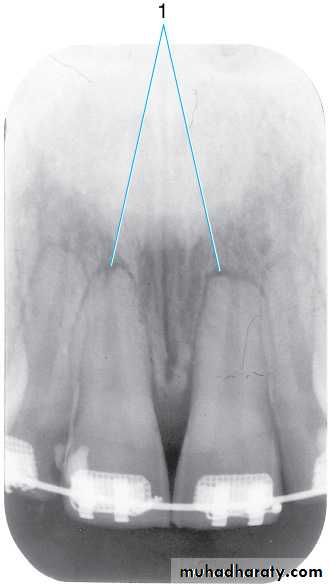

Soft tissue image of the nose (1). The resultant image of the soft tissue of the nose is often magnified to a large size. According to the rules of shadow casting , the further an object is from the film packet, the more likely that object will appear magnified. The tip of the nose is at an increased distance from the intraoral film packet, resulting in a magnification of the size of the nose.